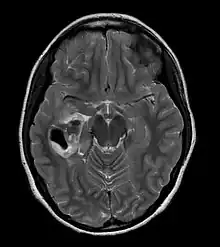

| CT scan of a brain with pleomorphic xanthoastrocytoma. The classic radiographic appearance is one of a superficially situated tumor, here a mural nodule, associated with an underlying cyst. |

- A CT scan of the brain, and/or an MRI scan of the brain and spine, will be performed. A special dye may be injected into a vein before these scans to provide contrast and make tumors easier to see.